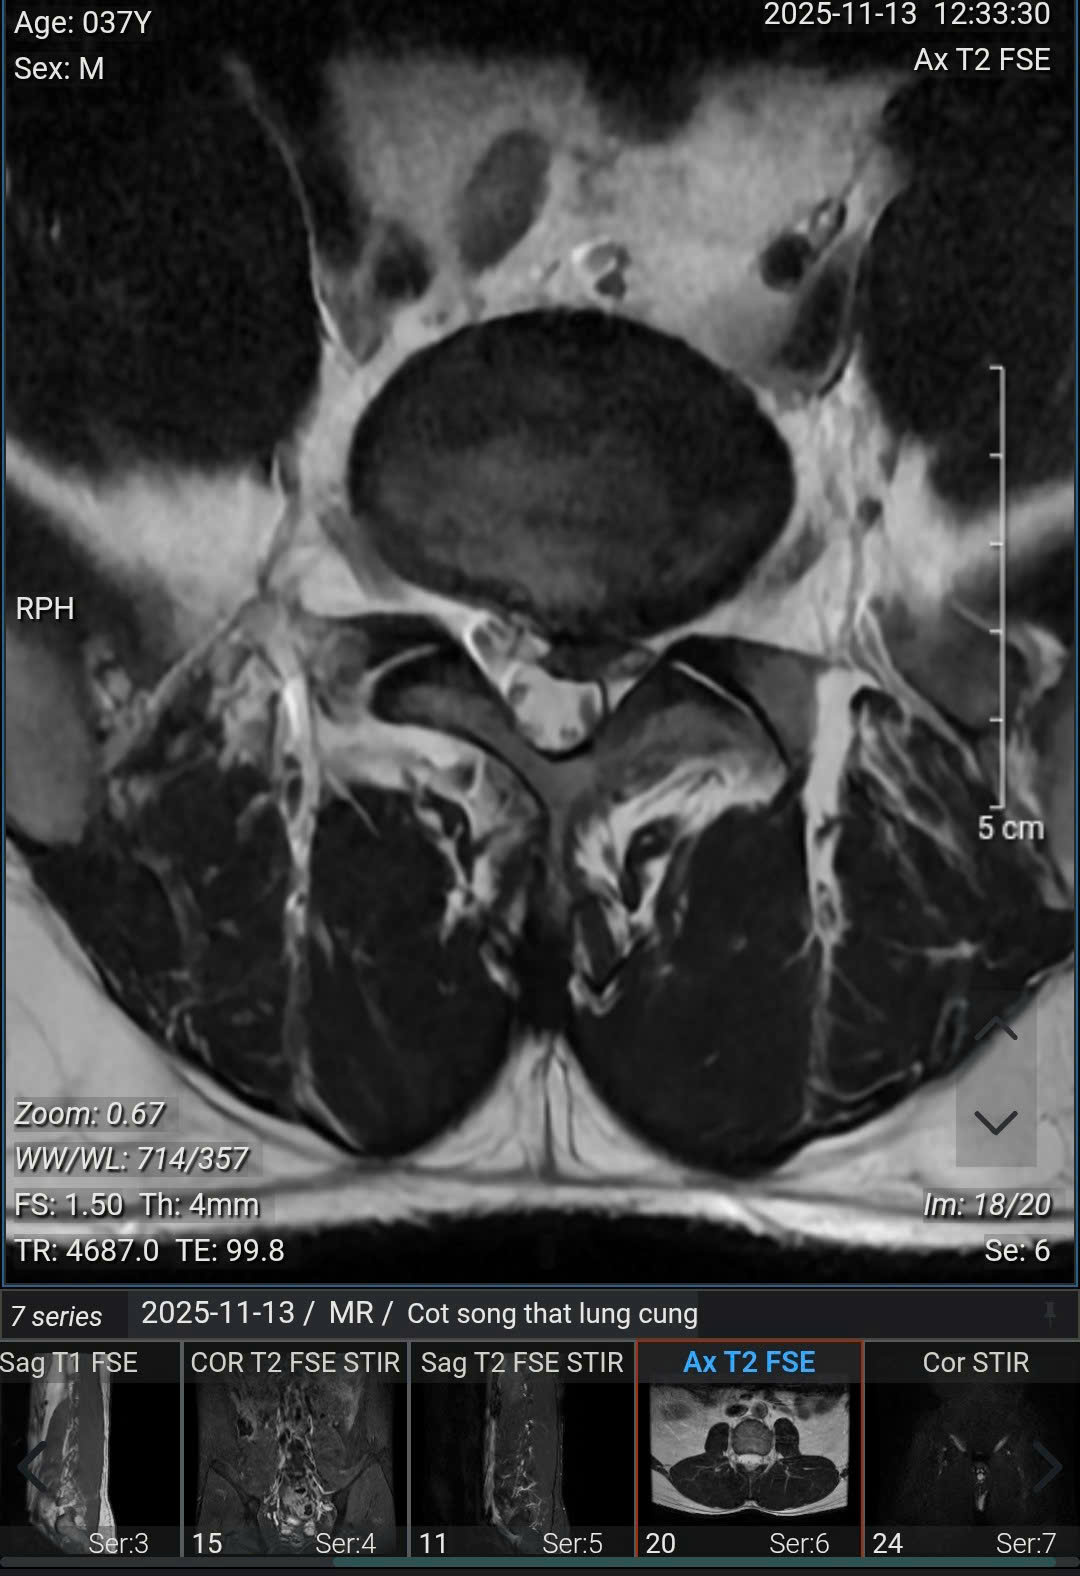

(Ảnh chụp MRI của anh Nam, 37 tuổi (Hà Nội)).

Kết quả chụp MRI cho thấy, bệnh nhân bị thoái hóa cột sống thắt lưng, thoát vị nội xốp các đĩa đệm từ L2/3 đến L5/S1, phình - thoát vị đĩa đệm L4/5 ra sau thể trung tâm gây chèn ép bao màng cứng, gây hẹp nhẹ ống sống, không gây chèn ép rõ rệt các rễ thần kinh; phình - thoát vị đĩa đệm L5/S1 ra sau thể trung tâm lệch trái gây chèn ép bao màng cứng, gây hẹp ống sống, hẹp ngách bên - lỗ tiếp và chèn ép các rễ thần kinh 1 bên ngang mức (trái > phải).